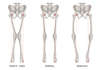

- Déformation d’axe du membre inférieur (Genu Varum ou Genu Valgum)

L’ostéotomie du genou est indiquée dans l’arthrose faible à modérée touchant le compartiment fémoro-tibial interne ou externe, avec un déformation d’axe du membre inférieur : Genu Varum ou Genu Valgum.

Habituellement, pour un Genu Varum (Jambe « à la lucky luke »), l’ostéotomie tibiale d’ouverture interne avec une hyper-correction en Valgus de 3° à 6° est recommandée. L’ostéotomie tibiale de fermeture externe est une technique difficile, avec des risques de lésions neurologique (Nerf sciatique poplité externe).

Pour le Genu Valgum (Jambe en X), il est préférable de réaliser une ostéotomie tibiale de fermeture interne. Il n’y a pas de consensus sur le degré de correction à obtenir. Généralement, en post-opératoire, l’objectif est d’obtenir un membre normo-axé (HKA = 180°).